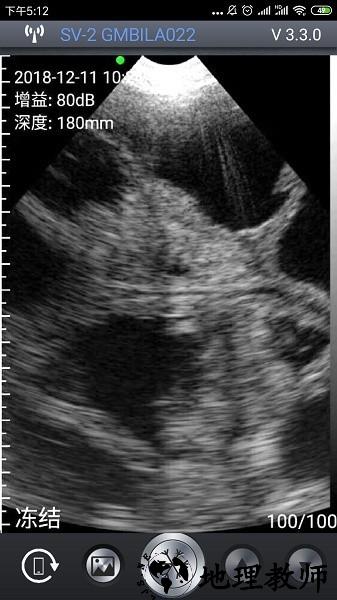

1、在进入APP后,屏幕左上角会显示当前时间、深度参数,若设备未连接或未启动探头,这些值将显示为--。

3、当探头正常工作且图像实时显示时,界面左上角会显示具体的增益,用户可据此调整图像清晰度与探测深度。

2、 成像精准:配套硬件协同工作,呈现高清晰度图像,辅助准确判断母猪怀胎情况。

2、实时图像显示:即时呈现超声扫描画面,便于快速查看与初步判断检测结果。